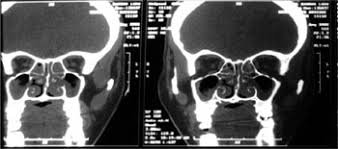

Mucormicosis Rinocerebral A Proposito De Ocho Casos Sciencedirect

Mucormicosis Rinocerebral A Proposito De Ocho Casos Sciencedirect from ars.els-cdn.com